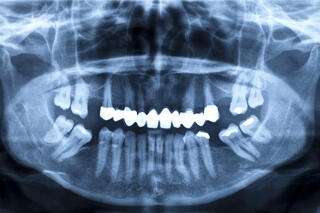

Protruding front teeth can be caused by several underlying problems, some of them dental and others skeletal. Dental causes can include crooked or crowded teeth, among others, that can generally be corrected with orthodontic care. Skeletal problems that can cause the front teeth to protrude include misalignment of the jaws or uneven jaw growth – conditions that typically require the help of a Singapore oral surgeon. Skeletal issues generally cannot be corrected through orthodontic treatment alone, but can be fixed with jaw surgery.

An overbite is when the upper teeth overlap the lower ones significantly when the mouth is closed. This can push the upper lip out, cause the chin to recede and make it difficult or impossible for a person to close the mouth comfortably, altering the facial profile and affecting appearance. As anyone who has been teased with the term “buck teeth” can attest, living with protruding front teeth can take a toll on self-esteem, self-confidence, which often affects quality-of-life. Moderate to severe cases can cause functional problems as well, such as reduced chewing and biting efficiency, poor speech clarity, jaw pain and excessive and uneven tooth wear, which can lead to serious dental problems and tooth loss.

When overbite is caused by dental problems, such as poor tooth positioning or crowding, orthodontic treatment can generally address the problem, correcting a person's bite and improving their appearance. However, when the issue has a skeletal component, corrective jaw surgery, technically called orthognathic surgery, is often the best means of resolving it.